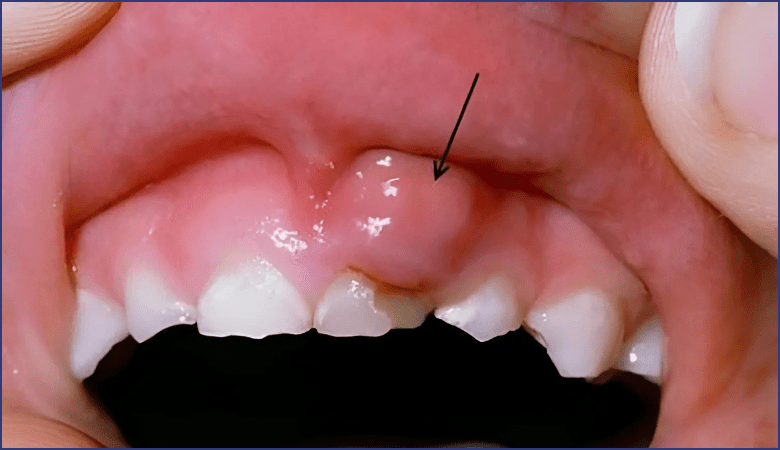

Sưng nướu răng hay còn gọi là viêm nướu, là hiện tượng mô nướu bị viêm do sự xâm nhập và phát triển của vi khuẩn trong các mảng bám không được làm sạch triệt để. Nguyên nhân chủ yếu xuất phát từ thói quen chăm sóc răng miệng kém hiệu quả, khiến vi khuẩn tích tụ lâu ngày gây tổn thương đến mô nướu. Đây là một vấn đề răng miệng khá phổ biến, có thể xảy ra ở cả trẻ em lẫn người lớn. Mặc dù không phải là bệnh lý nguy hiểm, nhưng nếu không được phát hiện và can thiệp kịp thời, sưng nướu có thể tiến triển nặng hơn, ảnh hưởng đến sức khỏe răng miệng tổng thể.

Sưng nướu răng là hiện tượng mô nướu bị viêm do sự xâm nhập và phát triển của vi khuẩn trong các mảng bám không được làm sạch triệt để (Nguồn: Internet)